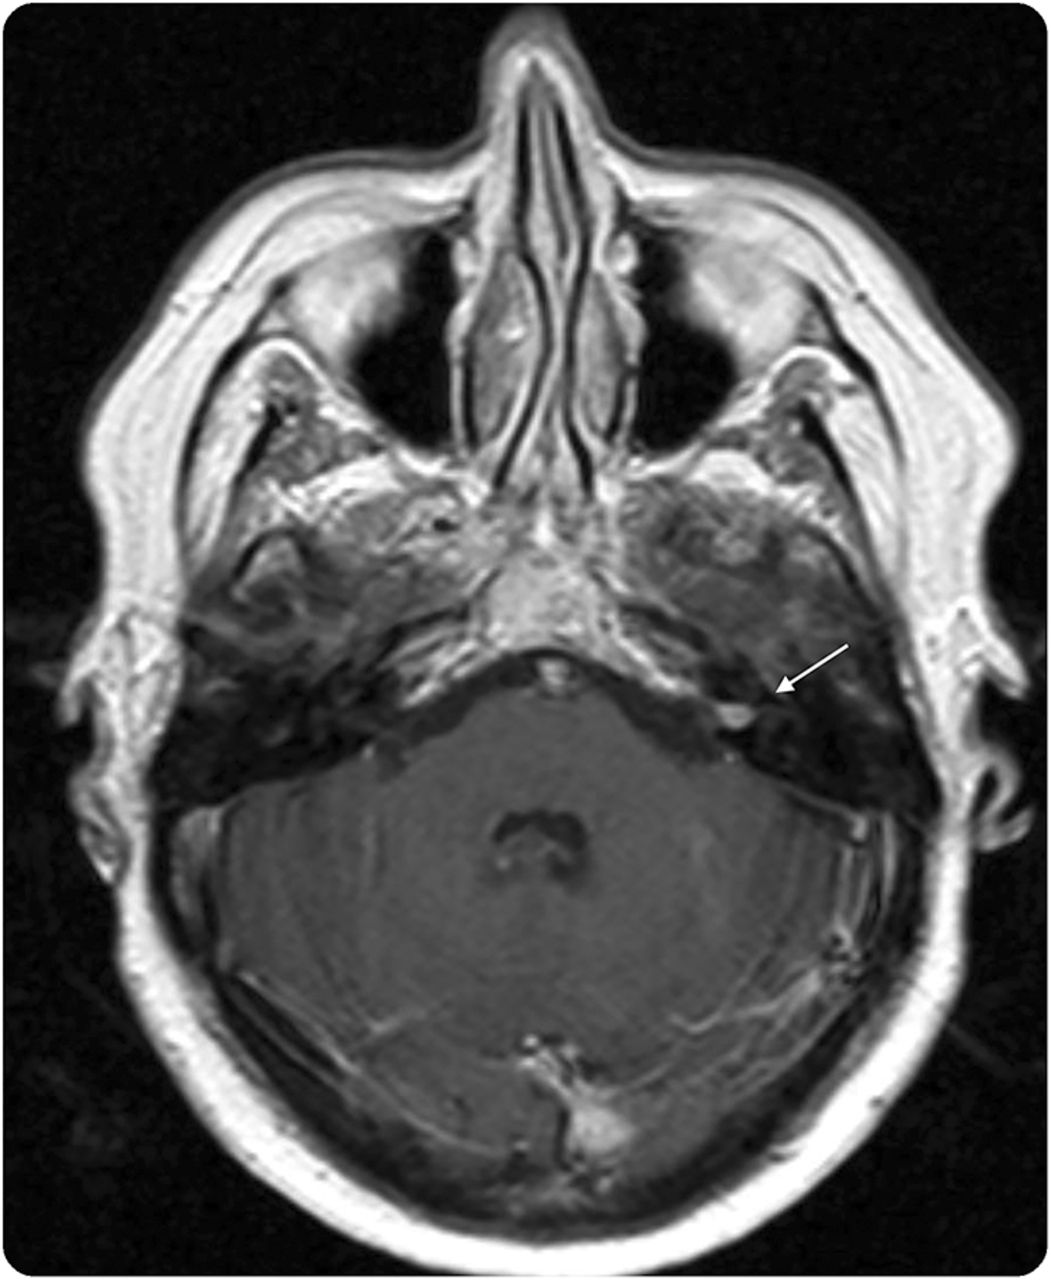

一个59岁的女人面对进步奔袭感音神经性听力损失。检查显示一个增强病灶内部听觉运河(IAC)符合前庭神经鞘瘤(图1)。